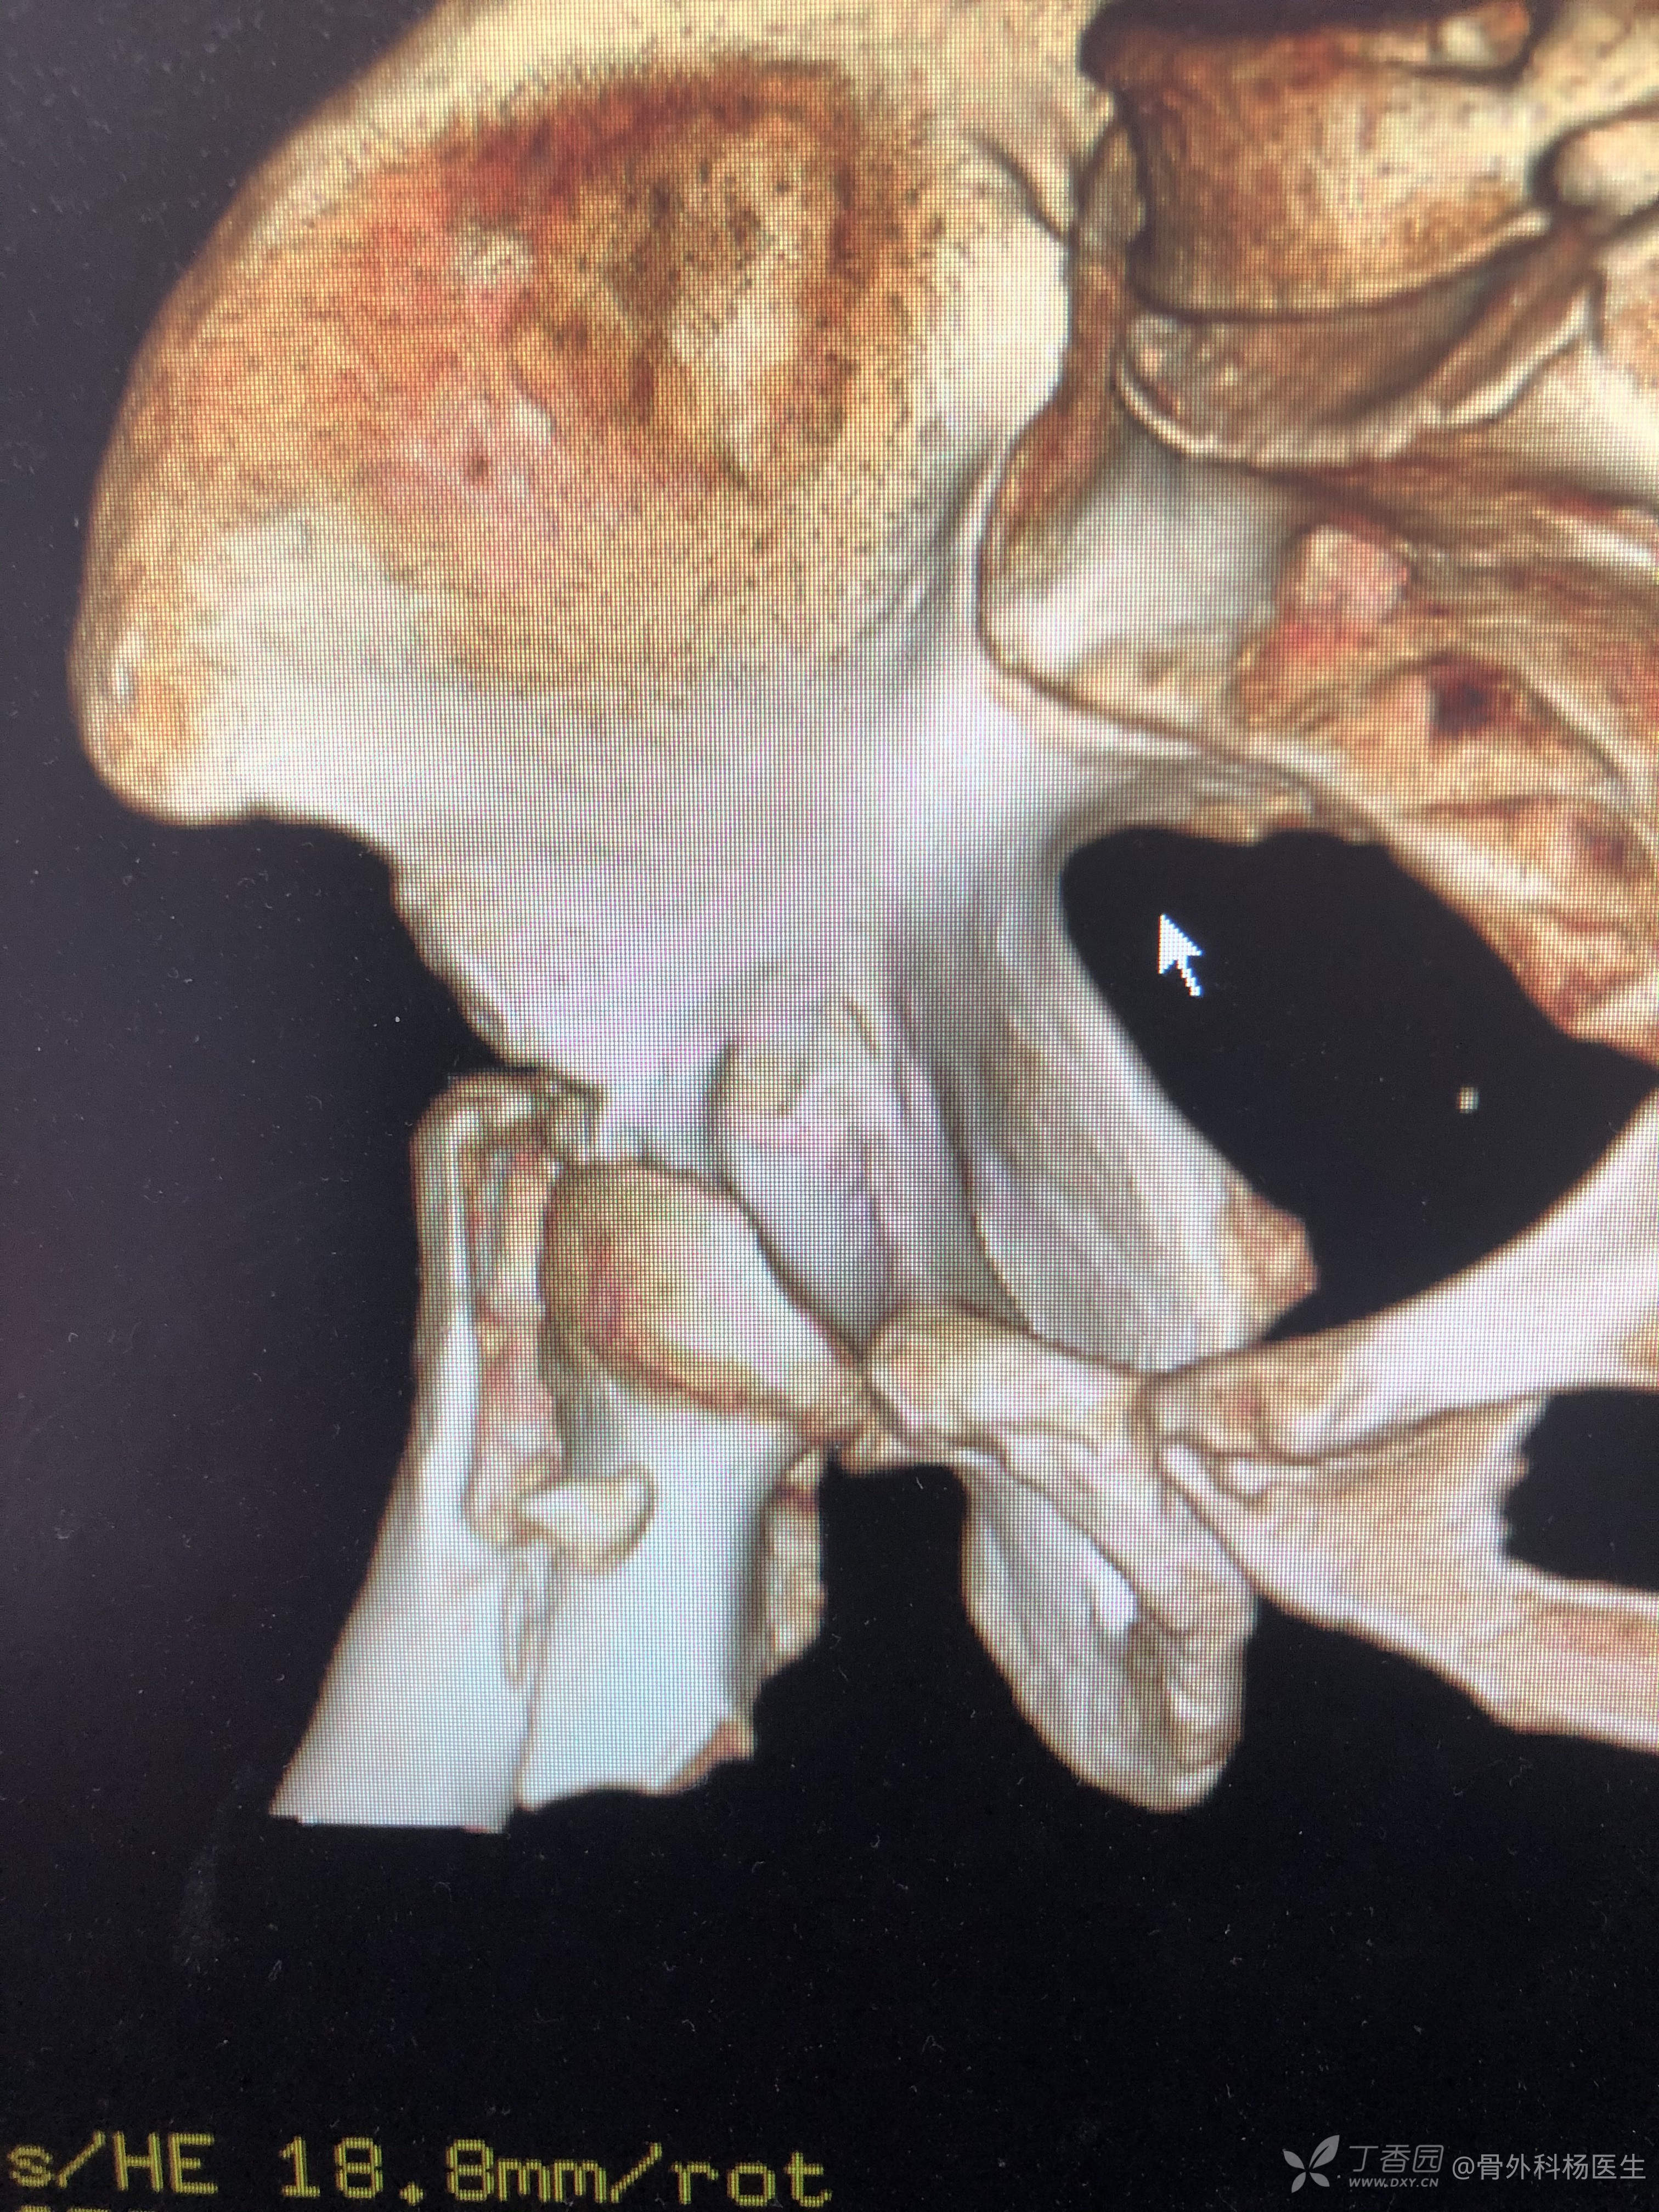

A1.3 骨折线经过小转子下方,如下图:

多见于年轻且骨质较好的患者。